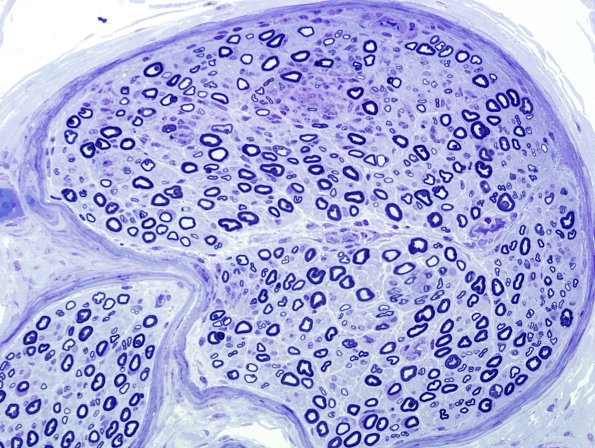

Case 8 No History ---- Diagnosis proven by ultrastructure. ---- Patchy demyelination and myelin debris demonstrate involvement of this fascicle. (Plastic section)